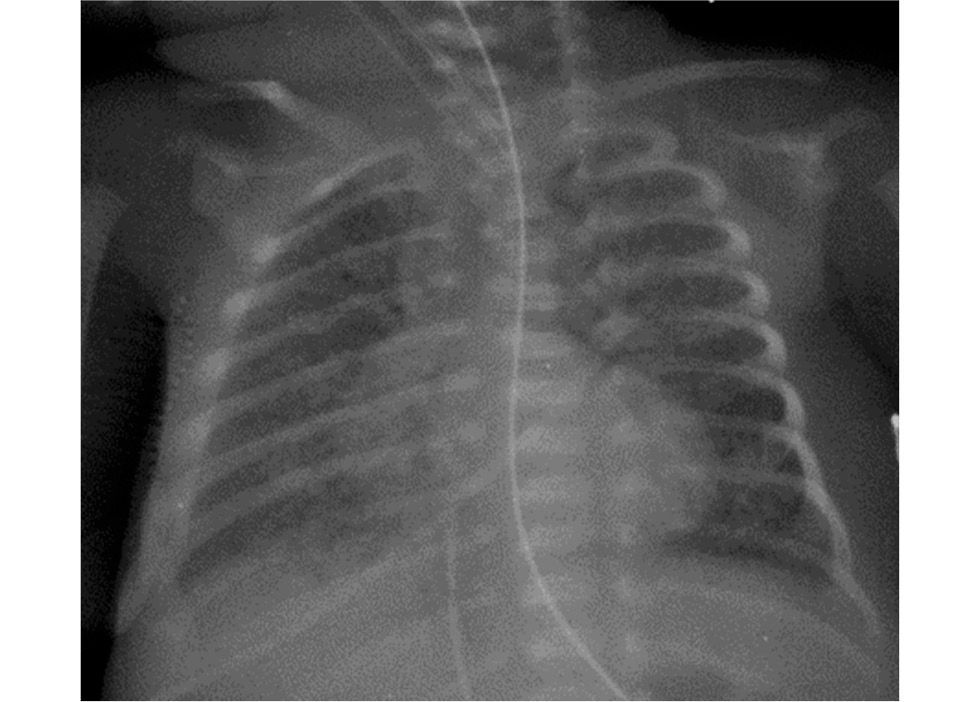

В динамике состояние было стабилизировано, получена положительная динамика со стороны лёгких, подтверждённая рентгенологически (рис. 2). На 17 сут жизни девочка была переведена на традиционную вентиляцию лёгких.

Рис. 2. Рентгенограмма органов грудной полости на 17 сут жизни: положительная динамика.

Fig. 2. X-ray of the chest organs on the 17th day of life: positive dynamics.

Через 2 сут клинический статус вновь ухудшился за счёт нарастания ДН, по результатам рентгенографии выявлен ателектаз нижней доли правого лёгкого (рис. 3).

Рис. 3. Рентгенограмма органов грудной полости на 19 сут жизни: ателектаз нижней доли правого лёгкого.

Fig. 3. X-ray of the chest cavity on the 19th day of life: atelectasis of the lower lobe of the right lung.